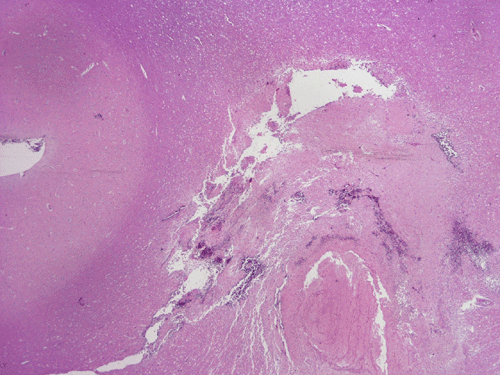

The followings are representative images from autopsy. Panel D to E are taken from the softened area. Panel G and H are taken from the blood vessels of the circle of Willis.